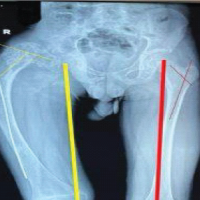

During the next 2 years, she had little pain but continued loss of ROM. At 26 months after the last operation, she developed a sense of instability, with the feeling that something was moving in the arm. Conventional radiographs showed that the custom tumor prosthesis had fallen into varus and was eroding through the humerus (Fig. 6).

Figure 6: Anteroposterior radiograph showing reduction of the fracture, secured in place with a fibular allograft strut and long plate. The humeral component gradually loosened and migrated into varus, as seen here.

Laboratory tests and aspiration showed no signs of infection. Magnetic resonance imaging of the shoulder showed a moderate-grade partial tear in the supraspinatus tendon (3–4 mm) but no evidence of tendon retraction. Because her pain became intolerable, she underwent another revision, and histological testing did not find any signs of infection. At the time of surgery, the humeral component was found to be completely loose. The humeral stem was removed manually along with the cement distally, with no difficulty. Specimens obtained at the time of surgery did not demonstrate any signs of infection on histological analysis. An allograft-prosthetic composite (APC) was then used to reconstruct the proximal humerus. The APC was constructed with a cemented short-stem humeral component (Zimmer Biomet) in the proximal humeral allograft. The APC was fixed internally to the existing humerus and previously placed allograft using 2 plates (Fig. 7).

Figure 7: Anteroposterior (a) and lateral (b) radiographs showing finished reconstruction using allograft and plate.